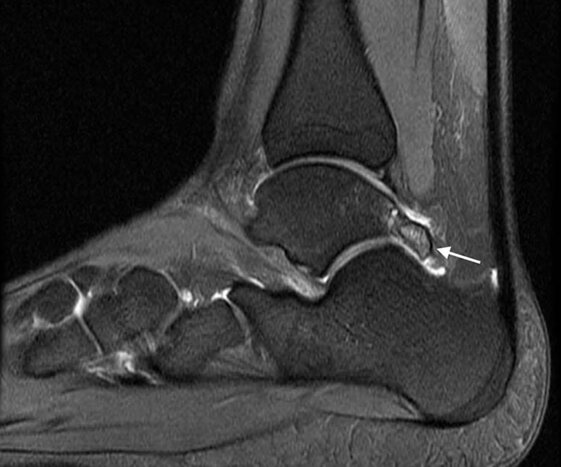

Os Trigonum

- Embriologicamente il corpo dell’astragalo e il suo processo posteriore sono centri di ossificazione differenti. Tra il settimo e il tredicesimo anno di vita è visibile un nucleo di accrescimento osseo, l’ Os Trigonum, che normalmente si fonde con il processo posteriore dell’astragalo entro un anno dalla sua comparsa radiografica. Se questo processo non avviene il corpo dell’astragalo rimarrà separato dall’os trigonum anche in età adulta diventando così un osso accessorio a volte doloroso. Circa 7 persone su 100 hanno l’os trigonum. Di solito l’osso è presente bilateralmente e ha forma triangolare e non supera 1cm di grandezza. Il tendine del flessore lungo dell’alluce è situato appena mediamente all’os trigonum e questo rapporto anatomico è causa della sindrome dell’impingement posteriore di caviglia (PAI), una tipica patologia dei ballerini (soprattutto di danza classica) e di chi in generale ripetutamente effettua una flessione plantare della caviglia causando un effetto “schiaccianoci” sulla caviglia posteriore che si infiamma cronicamente causando dolore ed impotenza funzionale e gonfiore posteriore associato che riduce ulteriormente la capacità di plantarflettere il collo-piede riducendo la performance dell’atleta o del ballerino.

Clinicamente i sintomi principali sono il dolore nella regione posteriore della caviglia ed il gonfiore associato che causano un’impotenza funzionale. La sintomatologia a volte può essere importante con un esercito acuto, in questi casi avviene una vera e propria frattura dell’os trigonum che si distacca dal corpo astragalico.

La diagnosi viene posta con una visita accurata e l’ausilio di una radiografia in laterale sotto carico e di una RMN ad alta risoluzione.

Il trattamento può essere conservativo o chirurgico. Inizialmente ci si avvale di terapie fisiche e crioterapia locale per il controllo del dolore e dell’infiammazione. L’eventuale trattamento chirurgico consiste nell’asportazione dell’os trigonum per via artroscopica con accesso posteriore. L’intervento è poco invasivo, in day-hospital, l’anestesia è loco-regionale, la ripresa è rapida e con buoni risultati clinici e funzionali seguendo un adeguato protocollo riabilitativo.

A sinistra esempio di immagine radiografica e a destra di immagine RMN che evidenziano voluminosi Os Trigonum che dovranno essere asportati per via artroscopica con accesso posteriore come nella foto sotto.